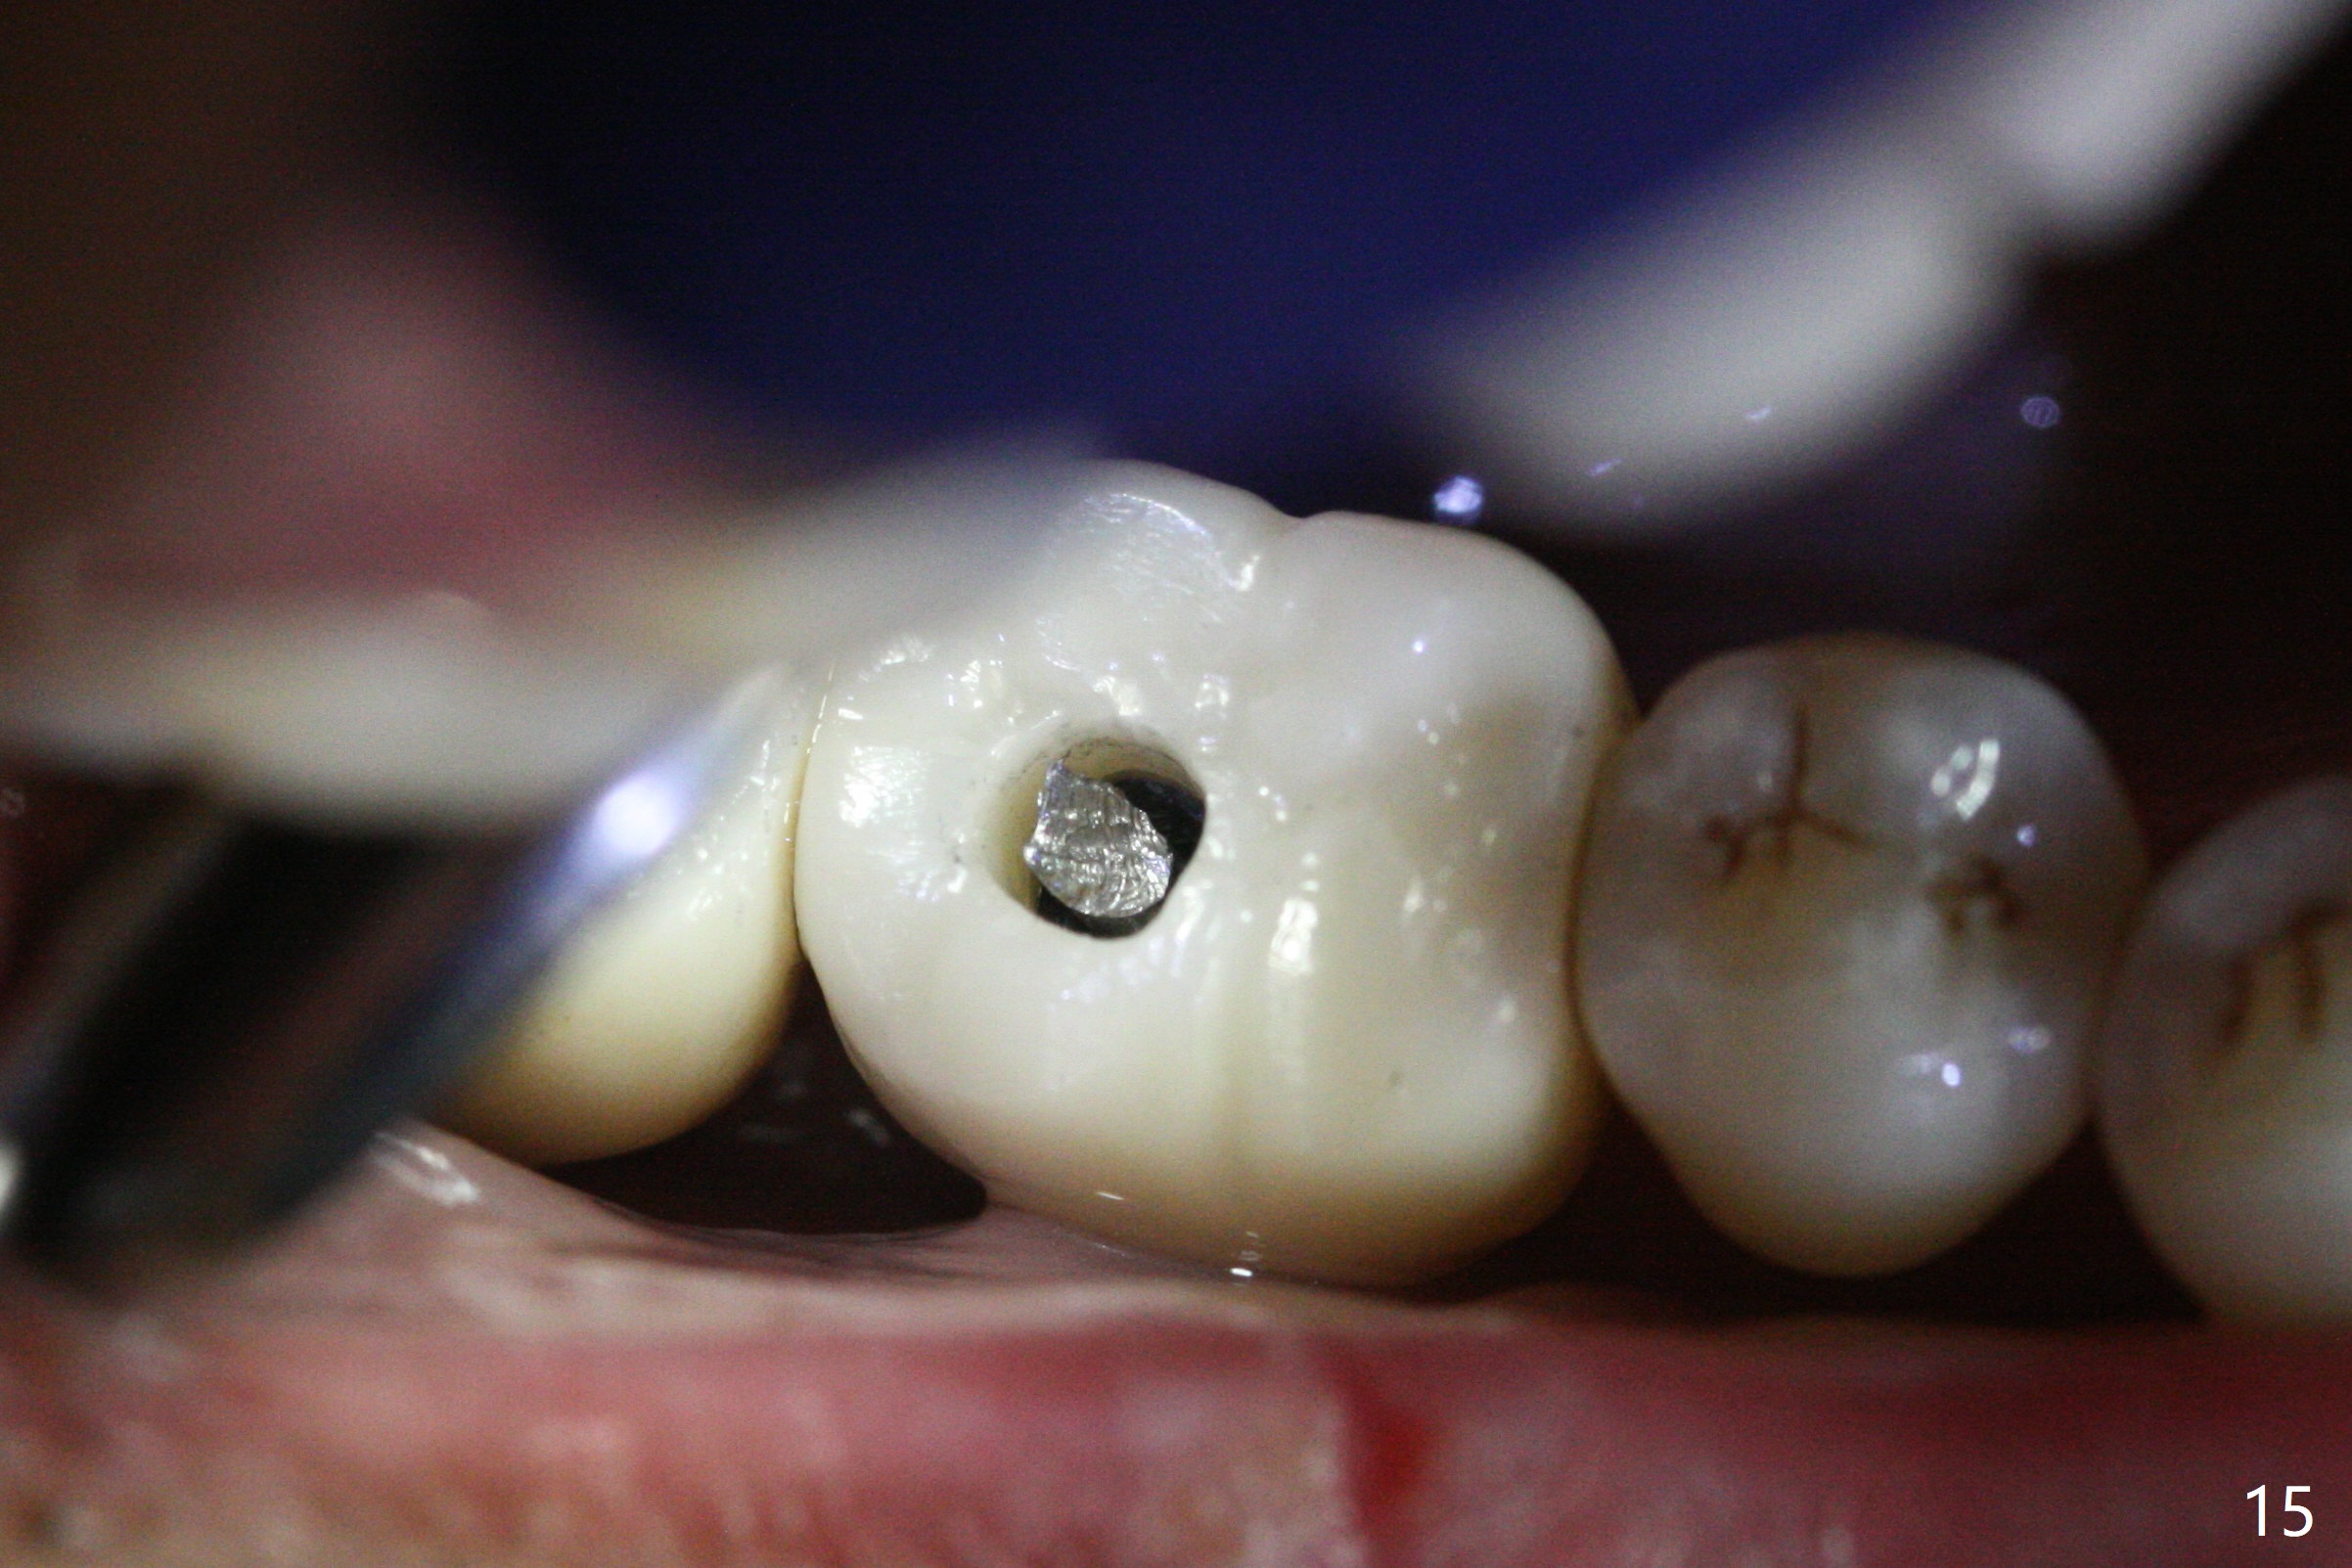

Extraction shows the large distal socket (Fig.1 D) and the thin and low septum (*) of the tooth #30. After Magic Split test confirms hard bone, osteotomy is initiated with 1.6 mm pilot drill with 11 mm stopper (Fig.2); there is 2.7 mm distance to the Inferior Alveolar Canal. Following Marking Bur, a 4.8 mm Magic Drill is used to finish the osteotomy with difficulty because of hard bone and ineffective local anesthesia due to infection. A 5x9 mm "dummy" implant is placed to determine the placement level relative to the distal crest (Fig.3 *). After removal of the dummy implant, an authentic one with the same dimension is placed with packing abundant allograft (.5-1.5 mm) and Osteogen (Fig.4 *); it appears that 4 to 5 threads (fins) of the implant (arrowheads) are engaged to the native bone for primary stability (>40 Ncm). Later more bone graft is placed distally (Fig.5 arrow). With the short implant placed not so deep, there is 6-7 mm clearance from the underlying canal (Fig.6). The patient is doing well 7 days postop (Fig.7). He feels that the provisional is too bulky buccally for the first 2 days postop. The buccal margin will be trimmed in another 2 weeks (dashed line). The patient in fact masticates on the right side postop. By the time he returns for provisional revision 1 months 10 days postop, he has mild pain. There is food entrapment. The provisional and the abutment are slightly loose, whereas the implant is stable with healing socket (Fig.8). A healing abutment is placed. The implant appears unstable nearly 5.5 months postop. The gap between the bone and implant seems to be large (Fig.9). The implant should have been larger and longer for fast healing. A healing screw is used instead. The site heals 10 months postop with an increase in bone density around the implant (Fig.10.) Prior to cementation of the final crown, the abutment is minimally exposed (Fig.11 (6.5x5.7(3) mm)). In fact the abutment screw becomes loose 2 months post cementation (1 year postop); it appears that crown/implant ratio is unfavorable (Fig.12). The implant is slightly placed mesially (cantilever). The patient cannot chew on the left. The tooth #19 is periodontally affected and the tooth #18 is missing. When bone loss is severe, the implant should be as large as possible and preferably tissue-level. The abutment screw is re-loosening 1.5 years post cementation (4 months post #19 socket preservation, Fig.13). The crown/implant ratio at #31 is more favorable than that at #30 (compare black lines). The crown at #31 has large contact area with the tissue-level implant (external), whereas the contact between the abutment and the bone-level implant is much less (internal). To prevent the abutment screw re-loosening (turning) in function, a screw driver (Fig.14 D) will be buried inside the crown/abutment after the screw is retightened. Make sure that the driver is in the middle of the access hole. Section the driver in situ obliquely (Fig.15); flat sectioning allows the driver to turn with the abutment screw in function. After insertion of plumber tape around the sectioned screw driver, use composite to fix the driver in place and seal the access hole (Fig.16). Occlusal check suggests weak link between the abutment and bone-level implant at #30.